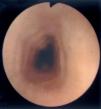

Al estudio endoscópico, en 2 pacientes (18,18 %) se observó una pérdida del patrón circular normal y tendencia a la traquealización (aspecto corrugado y patrón triangular con escasa insuflación) (fig. 1). En otros 2 pacientes se observaron lesiones puntiformes de aspecto blanquecino que correspondieron a acumulaciones de eosinófilos en el estudio histológico (figs. 2 y 3) y en un paciente se observó discreto prolapso cardial. En los otros 6 pacientes los resultados macroscópicos eran normales.

Figura 1.Aspecto corrugado o "traquealización" del esófago, hallazgo característico de esofagitis eosinofílica. El aspecto de anillos transversales se corresponde con contracciones intermitentes de la capa muscular circular.